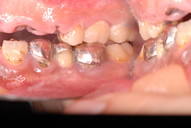

最初の状態です。若いのにすぐ外れる入れ歯をいれていらっしゃいました。

DSC_0167DSC_0162

DSC_0166DSC_0165

DSC_0164

そしてひとまず終了した状態です。

DSC_0018DSC_0023

DSC_0027

このように綺麗になりましたが元の健康な状態になったのではないのです。ばい菌が歯の周りから採れていなければ元の木阿弥。